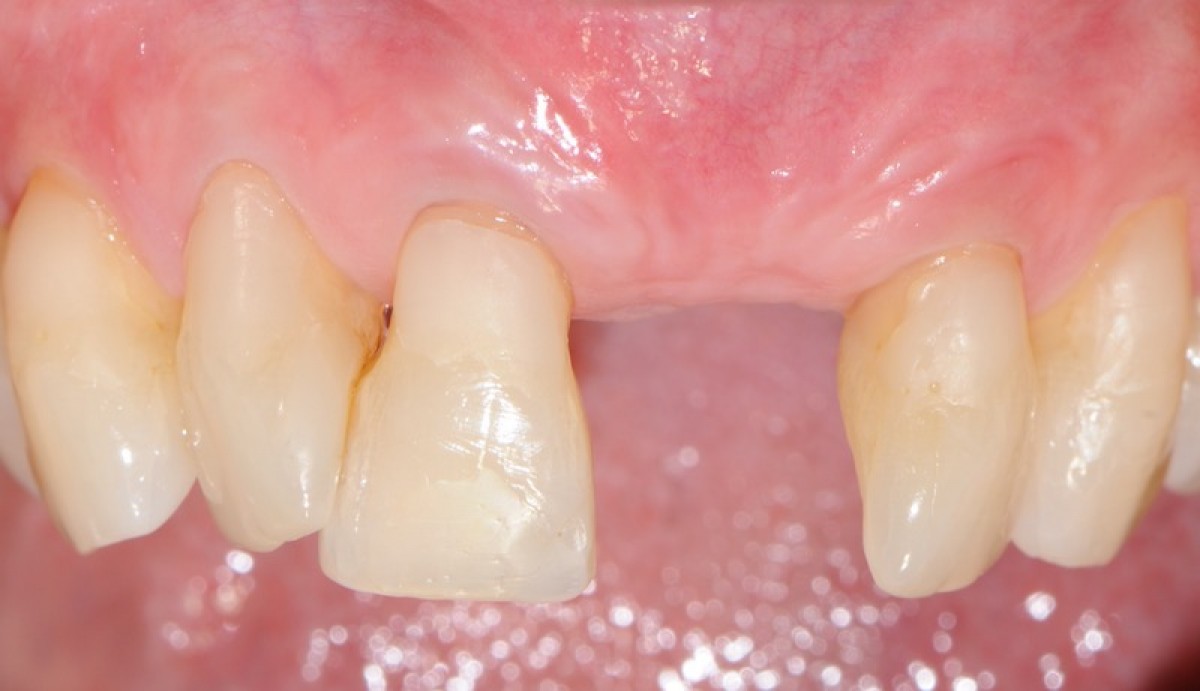

• aesthetic performance provided by the socket sealing material (T4).

• the mean colorimetric score ∆E between the regenerated site and the surrounding gingiva was 3.76 (3 to 6.55).

Seven out of 10 patients reported an excellent aesthetic integration of the matrix (∆E < 3.7).

Preliminary results from this study suggest that this new xenogenic porcine-derived collagen matrix could represent a valuable alternative to allow second intention healing of post-extractive sockets filled with a xenogenic bone substitute or with an immediate submerged implant. New randomized clinical trials are needed to confirm the preliminary results obtained in the study and evaluate the long-term benefits.